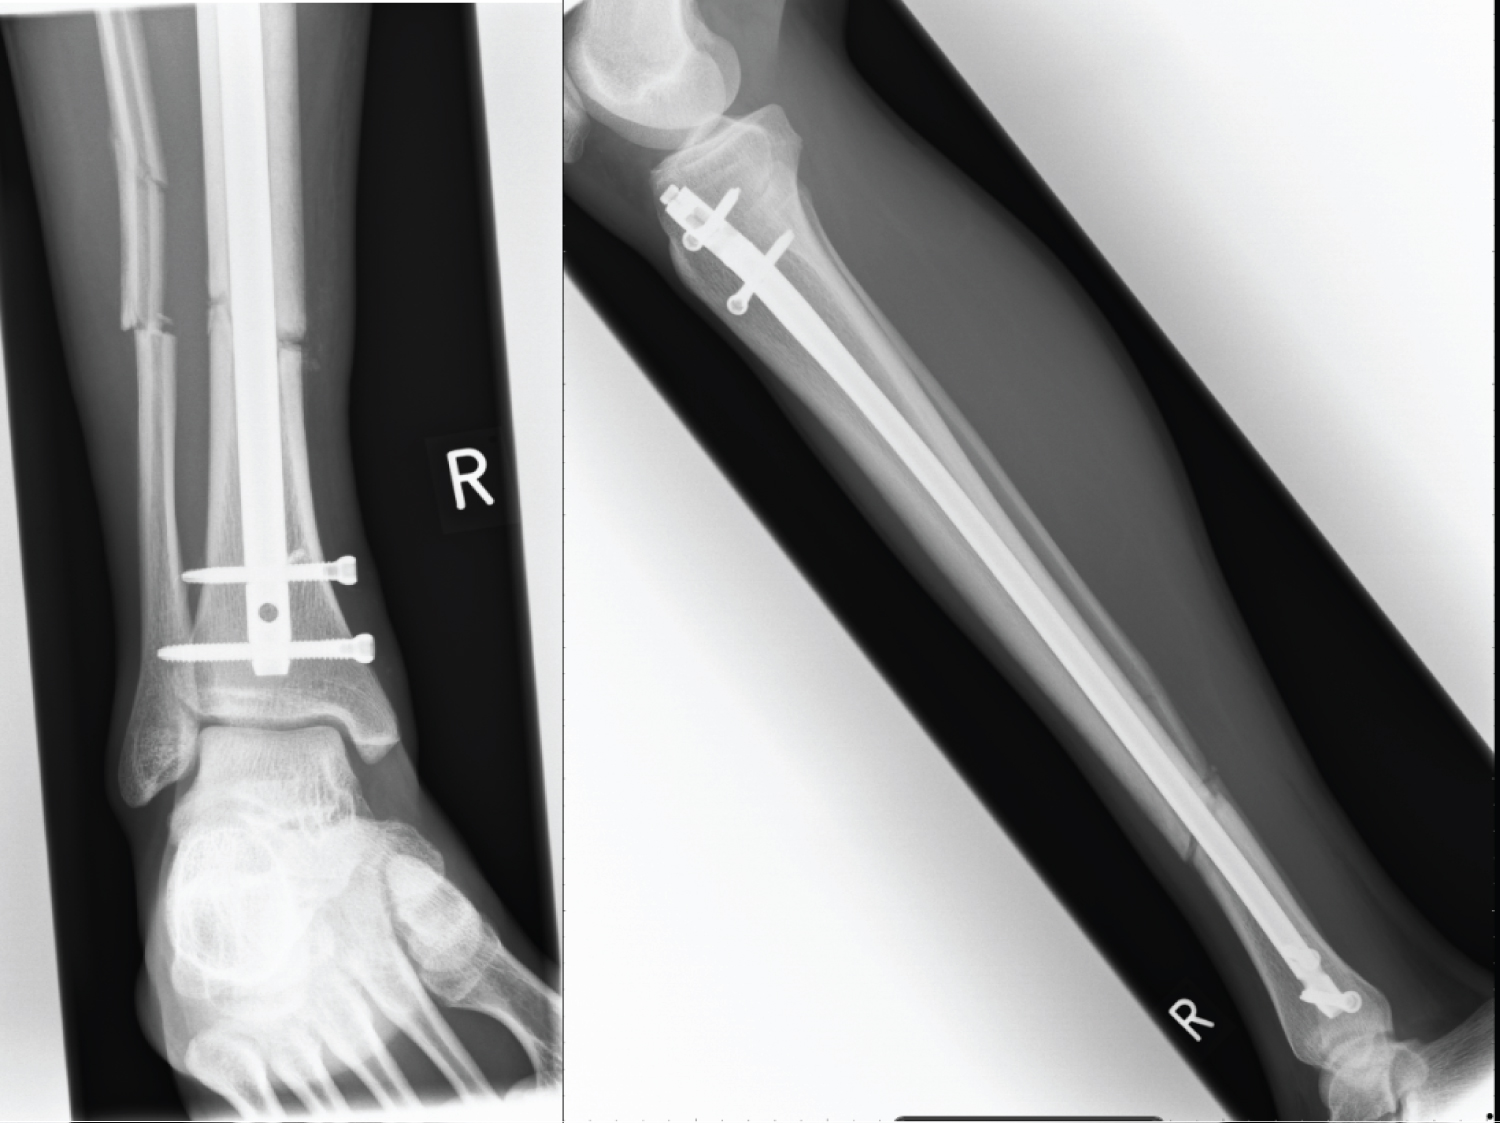

A 20 year old man suffered a closed, oblique fracture of his right tibial diaphysis at the junction of the middle and distal third with an associated fibula fracture whilst playing football (Figure 1). His tibia was stabilised with an antegrade, reamed, intramedullary nail and proximal and distal bolts, on a planned trauma list. The position on intraoperative fluoroscopy and post-operative radiographs show an appropriate reduction and position of the nail (Figure 2). Immediate weight bearing as pain allows was commenced post-operatively and after clinical and radiographic union, was permitted to return to sport and work as a crane driver.

Figure 1: AP + Lateral X-ray prior to surgical intervention. View Figure 1

Figure 2: AP + Lateral X-ray 4 weeks post ORIF. View Figure 2